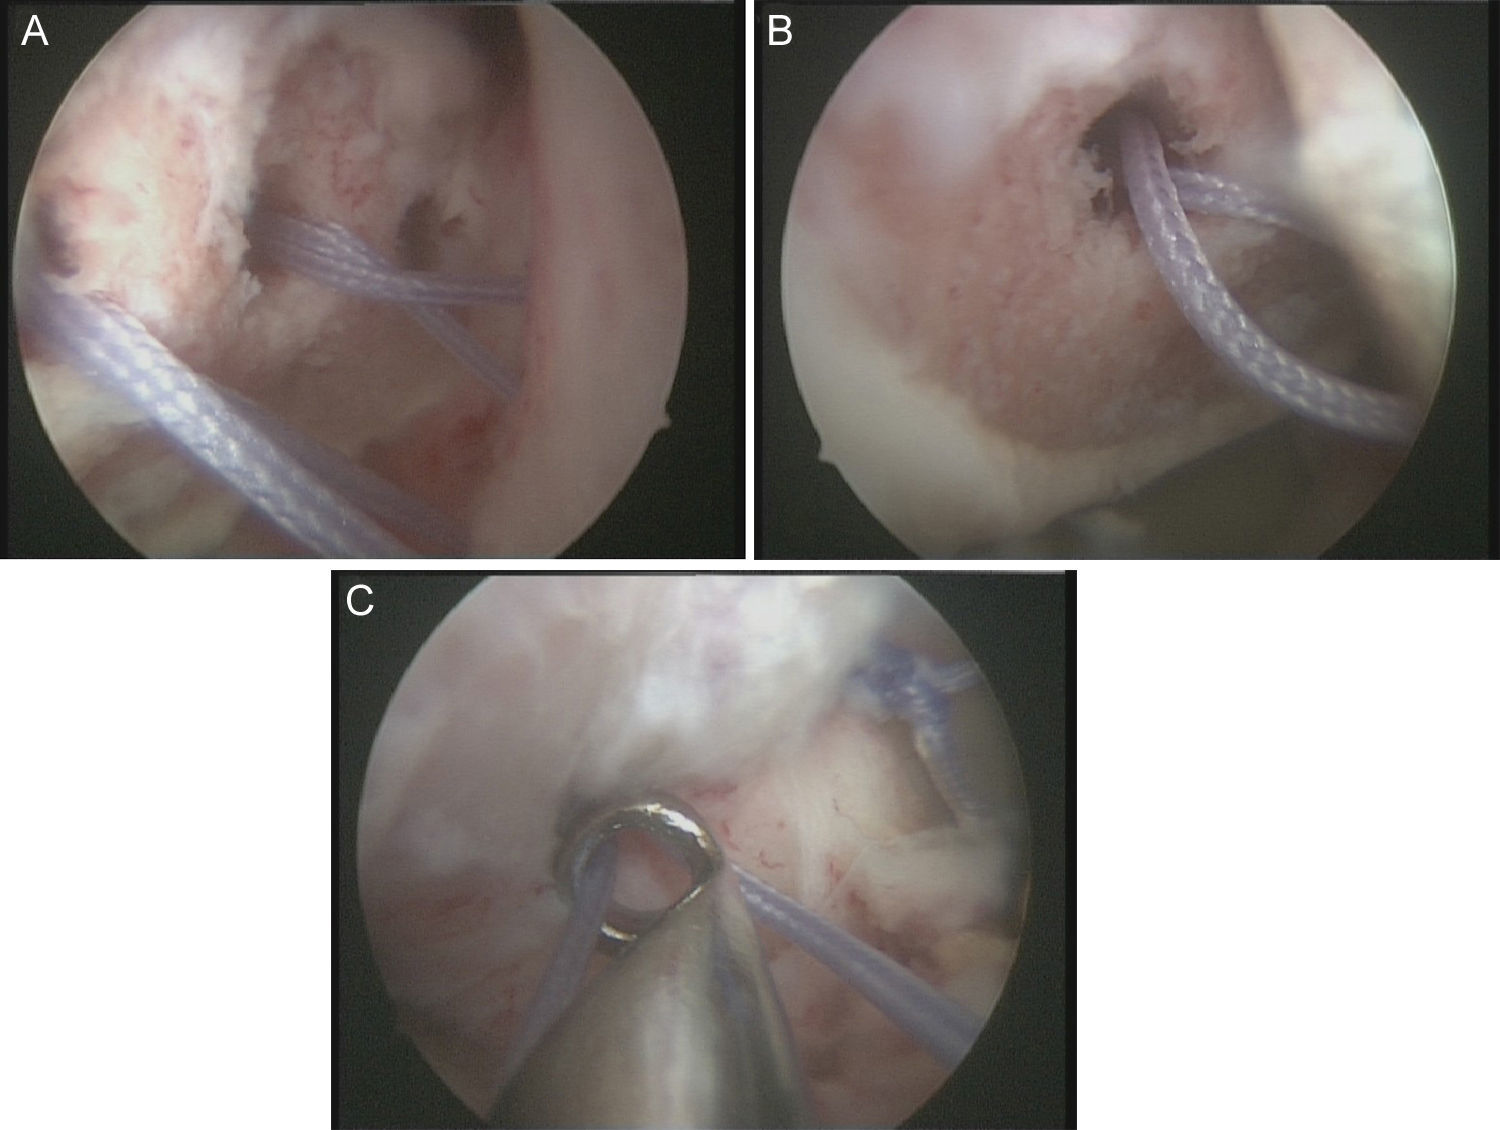

Técnica quirúrgicaBajo anestesia general y locorregional (bloqueo interescalénico), se intenta reducir el hombro de forma cerrada. En caso de no conseguirlo se coloca al paciente en decúbito lateral con tracción de unos 5kg y, siguiendo la técnica descrita por Verma5, se introduce un «Wissinger» por el portal posterior estándar, el que empleamos para la artroscopia de hombro. Con el «Wissinger» a través del portal realizamos tracción de la cabeza humeral hacia lateral, apoyándonos en la cápsula y en la parte posterior del manguito, no en el hueso. Habitualmente con esta maniobra conseguimos introducir la cabeza humeral en la glenoides y podemos pasar a realizar la artroscopia de hombro. En caso de no conseguir una reducción, pasaríamos a realizar una reducción abierta con el paciente en posición de silla de playa y con una vía de abordaje anterior al hombro. Con el hombro reducido se realiza la artroscopia de hombro. Se emplean los portales posterior, anterosuperolateral, anterior, portal de Wilmington y portal posteroinferior. Se estudia la lesión de Hill-Sachs inverso, la relación con el tendón del subescapular y la lesión del labrum posterior (fig. 2, figs. 3 y 4), el resto del labrum y el manguito de los rotadores. Hay que limpiar bien la articulación, extirpar todo el tejido fibroso, liberar el labrum posterior de las adherencias a la glena, preparar el lecho óseo de la glena antes de colocar los implantes (en el caso 1 se emplearon 2 implantes Lupine BR [DePuy Mitek, Raynham, MA], y el caso 2 con un Gryphon BR [DePuy Mitek, Raynham, MA] cargado con doble sutura), realizar la reconstrucción capsulolabral con un pasador directo o indirecto, anudar y cortar las suturas. Una vez reparadas las lesiones soltamos el brazo del sistema de tracción y comprobamos la relación de la cabeza humeral, del defecto óseo anterior con la glenoides, al hacer rotaciones del hombro (sobre todo si hay riesgo de «enganche» con la rotación interna), y decidimos si fijamos el tendón del subescapular en el defecto óseo humeral anterior, tal y como describió Krackhardt6.

No es estrictamente necesario que reproduzcamos un enganche de la lesión de Hill-Sachs inversa para decidir realizar el remplissage inverso. Con la óptica en el portal anterosuperolateral liberamos el tendón del subescapular, su cara anterior y posterior. Preparamos el lecho óseo de la cabeza humeral, extirpando todo el tejido fibroso de la lesión de Hill-Sachs inversa, con el sinoviotomo, la fresa de hueso o periostotomos, hasta obtener hueso sangrante. Entonces desde el portal anterior, insertamos los implante en el defecto óseo (en el caso 1 un 5,5 Healix BR [DePuy Mitek, Raynham, MA] con 2 suturas UHMWPE [Orthocord; DePuy Mitek]) en el tercio superior y en la zona más medial del defecto (fig. 5), y en el caso 2 insertamos 2 Gryphon BR Healix BR (DePuy Mitek, Raynham, MA) con 2 suturas UHMWPE (Orthocord; DePuy Mitek), uno inferior y otro superior en la zona más medial del defecto óseo. Recuperaremos las suturas desde un portal anterosuperior accesorio y con una pinza para atravesar el tendón (Penetratror DePuy Mitek, Raynham, MA) a través del portal anterior, atravesamos el tendón del subescapular y recuperamos las suturas. Daremos puntos colchoneros, uno inferior y otro superior, para conseguir un buen contacto del tendón con el hueso, separando los puntos entre 1 y 2cm (fig. 6). Podemos ayudarnos con un empujanudos a través del portal anterosuperior accesorio para el manejo y recuperación de las suturas, acercándolas a la boca de la pinza penetrator, tratando de no mover en exceso la pinza una vez atravesado el tendón, para evitar lesionar el tendón y el cartílago. Manteniendo el brazo en 35-40° de rotación interna anudamos primero el punto inferior y luego el superior (figs. 7 y 8).

Caso 1, hombro derecho. A. Vista desde el portal ASL de la lesión de Hill-Sachs inversa con el implante en el tercio medial del defecto óseo. B. Imagen después de hacer los nudos; podemos ver el tendón del subescapular rellenando parcialmente el defecto óseo de la cabeza humeral, con la cabeza centrada en la cavidad.

Caso 2, hombro izquierdo. A. Visión desde el portal ASL de la cara posterior del subescapular con los 2 implantes en la parte inferior y superior del defecto óseo. B. Imagen tras el anudado del punto más inferior. C.

Imagen de la cara anterior del subescapular tras el anudado del segundo punto.